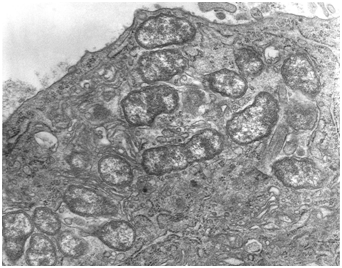

The most distressing factor of ebola pathogenesis of EVD is the fact that the Ebola virus is able to cross the placenta and infect the amniotic fluid and fetus. Furthermore, after a woman has survived Ebola, and viraemia has resolved, the products of conception (POC) remain NAAT positive, frequently with results signifying high virus levels5 (Figure 1).

Figure 1 Ebola virus under electron microscope view.